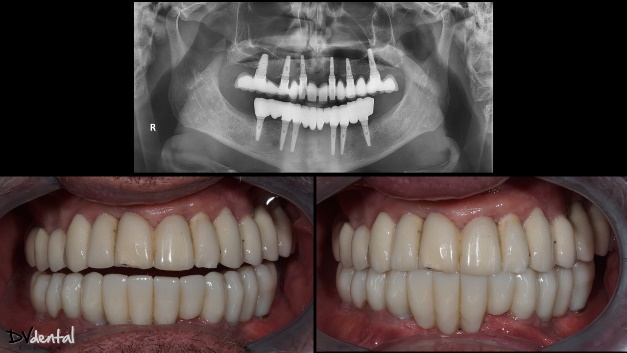

Before the permanent prosthesis, a prototype of it has been created for intraoral try-in. This is a good way to check the fit of our prosthesis clinically and radiographically while assessing the aesthetics simultaneously. After the successful try-in, the manufacturing of the permanent prosthesis (Zirconia full contour on Ti bases) will proceed. Finally, periapical X-rays show that the permanent prosthesis fits excellently, and the aesthetic outcome was exactly as planned, the patient is really happy about the result.

Fig 22: The intraoral photos after treatment.